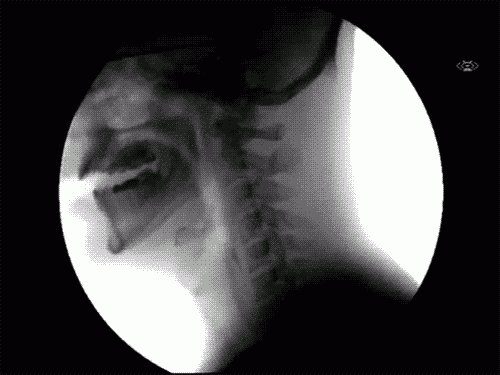

1. Yemeği nasıl yuttuğumuzu merak ediyorsanız işte görüntüsü: